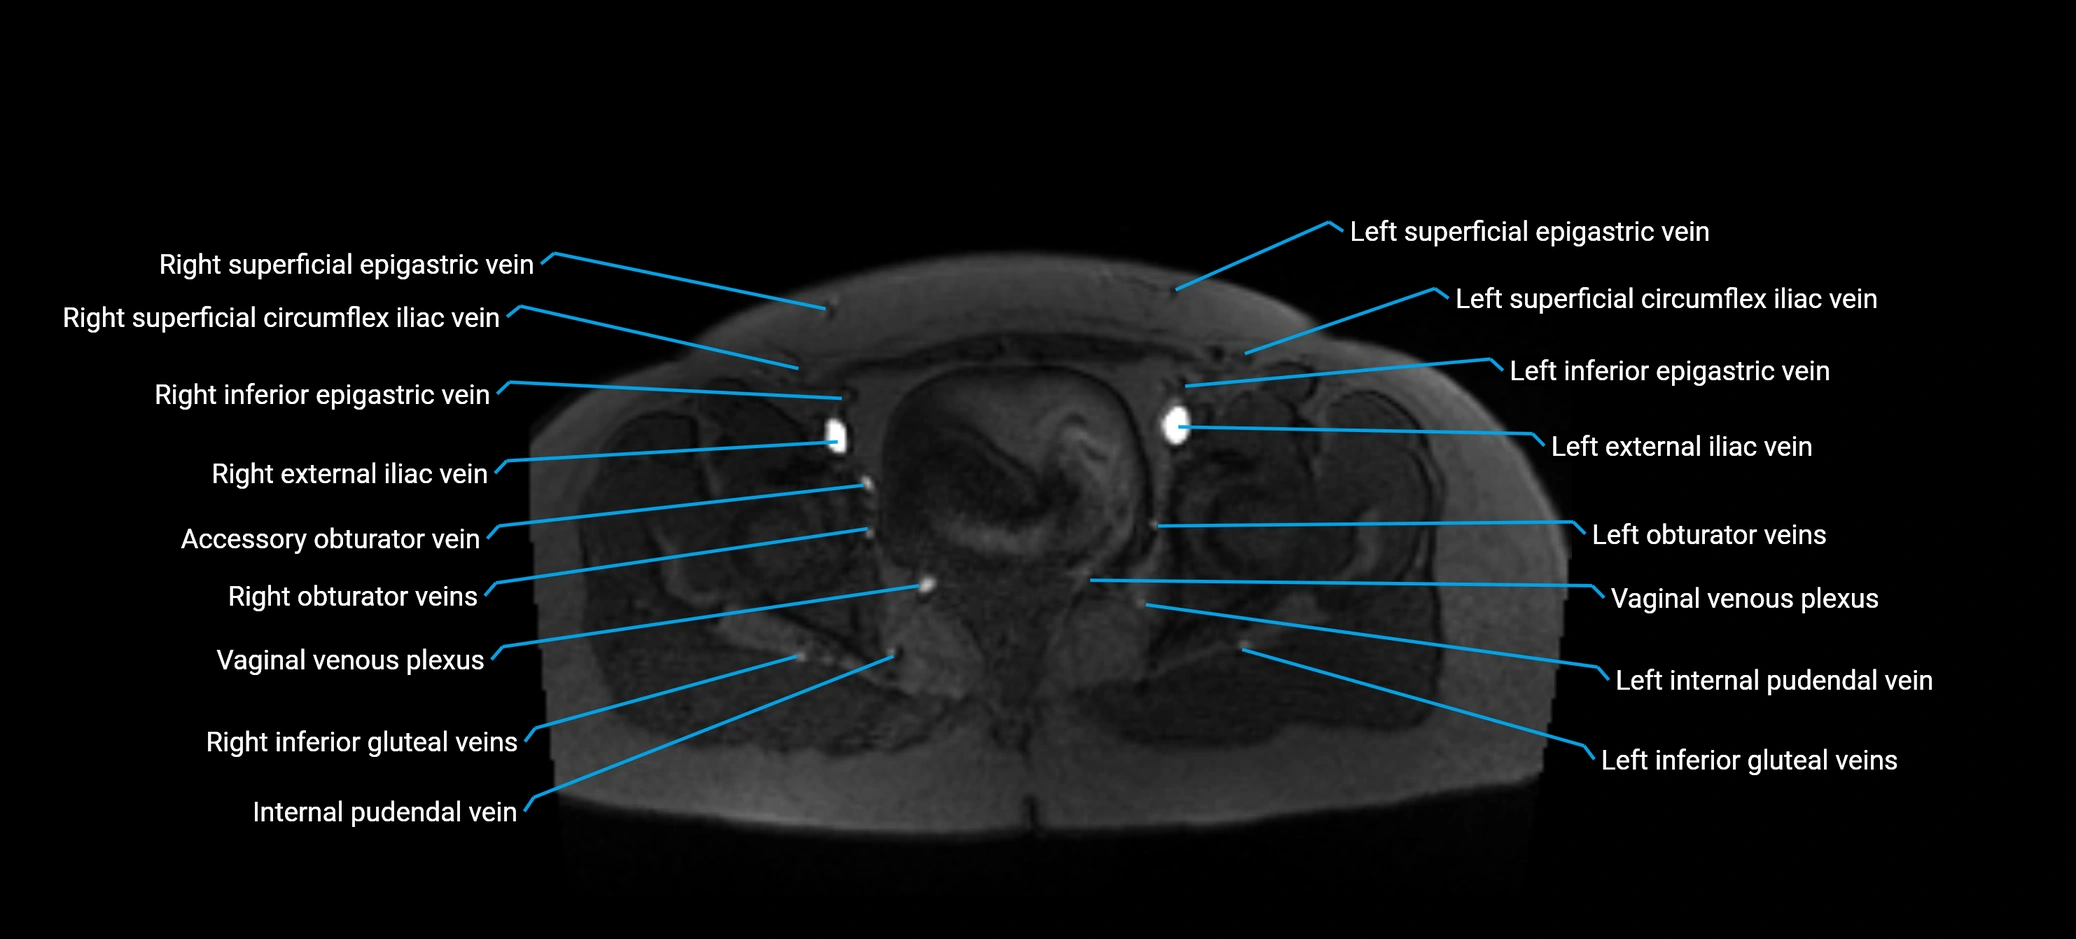

MRI image

image